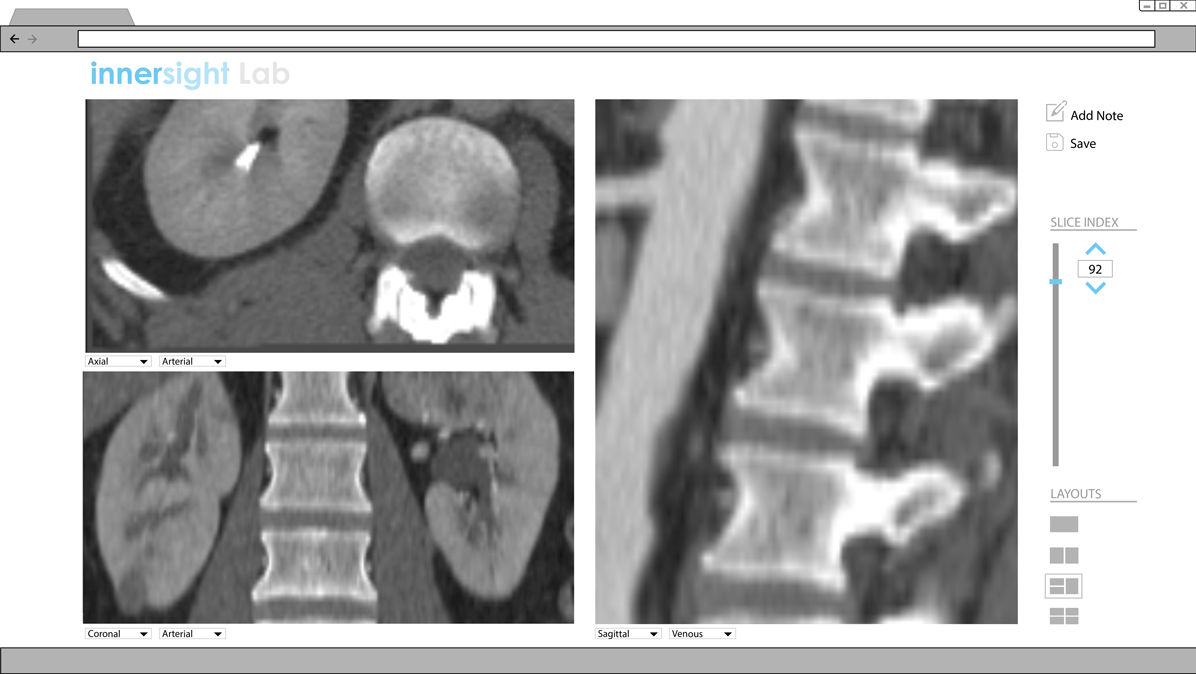

Existing Interface

The existing interface has a number of shortcomings, both in terms of its appearance and interactivity.

In terms of appearance, the positioning of the buttons are not in the most convenient location. The icons do not communicate their functionality straight away. Furthermore, the pop-up window that appears unnecessarily covers a large portion of the 3D model. It is annoying to close and reopen these windows numerous times. In terms of functionality, it is not explained to users that the left, middle and right buttons on the mouse are associated with rotate, zoom and panning functions. Overall, the existing interface offers a number of opportunities for improvement, to improve the user experience.